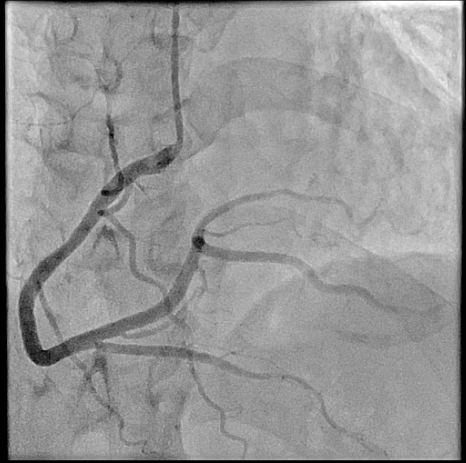

The procedure was performed via left radial artery access. The right coronary fistula was engaged with a 6F AL1 guide catheter. A 5F microcatheter advanced an ASAHI Sion Black wire into the fistula tract. Given the fistula¡¯s large size and high flow, a two-device closure strategy was employed. A 7-mm AMPLATZER Vascular Plug 4 was initially deployed proximally, achieving partial flow reduction. To ensure complete occlusion, an 8-mm AMPLATZER Vascular Plug was subsequently positioned at the ostium. Final angiography confirmed marked flow reduction in the fistula while preserving native RCA flow. The small LAD fistula was left untreated due to minimal shunting. The procedure was completed without complications, and radial hemostasis was achieved.

Large coronary arteriovenous fistula cause heart failure by chronic volume overload from left-to-right shunting. Transcatheter closure offers definitive treatment while avoiding surgical risks. In this case, a dual-plug technique achieved complete occlusion of a high-flow fistula without compromising coronary perfusion. Symptom resolution after the procedure, combined with guideline-directed medical therapy, underscores the importance of eliminating hemodynamic burden in fistula-related heart failure with reduced ejection fraction. This case supports percutaneous closure as a safe, effective strategy in selected patients.